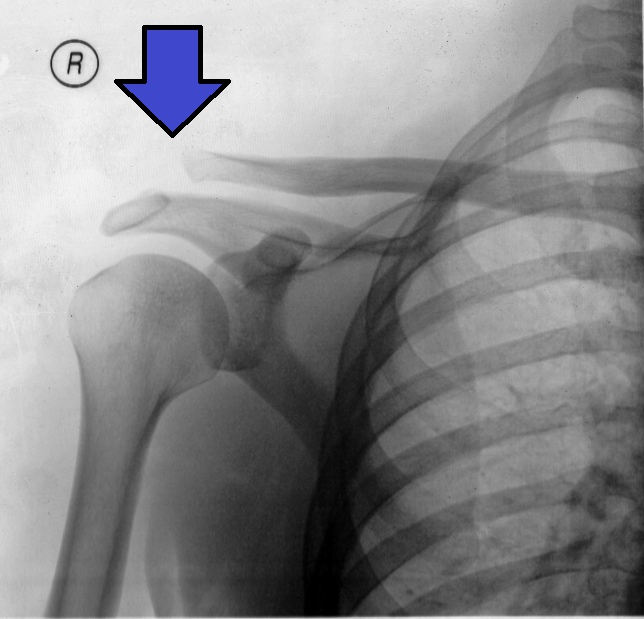

AC Joint Sprain

Acromio Clavicular Joint (ACJ) injury is most often caused by trauma following a fall directly onto the shoulder. These are commonly seen in rugby, after a bike accident or with a heavy fall onto the shoulder. The ACJ is also a common site of arthritic changes, particularly with a history of trauma.

ACJ is often graded depending on the severity of the injury using the Rockwood classification (see table below). It is important to establish the grade of your injury as there are different management approaches for each grade. X ray can be a useful tool in diagnostics but studies have shown that there are weak correlations between x ray findings and level of pain/disability experienced. It is vitally important that you are assessed to establish the extent of injury and any functional limitation to guide your management.Rockwood Classification Definitions (adapted from Black, 2013)

With more significant injuries you can notice a ‘step deformity’ when looking in the mirror. This is where the clavicle (collar bone) sits slightly proud to the acromion of the shoulder.